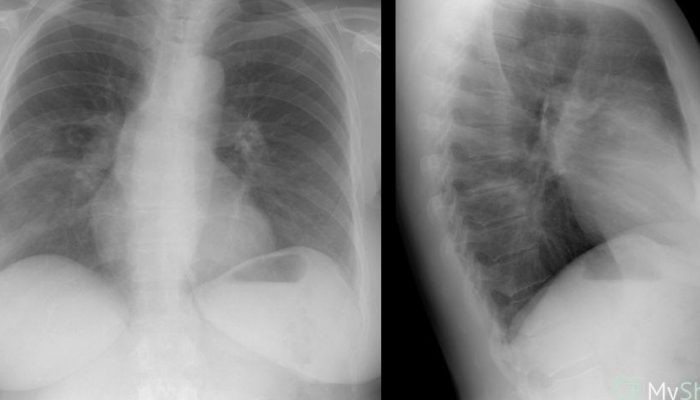

Быстро прогрессирующая интерстициальная пневмония представляет собой серьезное заболевание. Ее признаки включают высокую температуру, сухой и продолжительный кашель, а также затрудненное дыхание. Если своевременное лечение не будет проведено, то через несколько дней может возникнуть дыхательная недостаточность. Рентгенологическое обследование часто показывает наличие двустороннего распространенного затемнения легких, и основной метод диагностики заключается в изучении гистологического материала.

Используя рентгенографию, выявляются одинаковые изменения в легких на их краях («мутное стекло»).

Острая

Этот вид пневмонии начинается внезапно, симптомы напоминают грипп – повышается температура, появляются озноб и мышечные боли. Очень быстро развивается сильная одышка, которая может привести к нарушению дыхания и в тяжелых случаях потребовать использования искусственной вентиляции легких. Характер течения болезни схож с респираторным дистресс-синдромом у взрослых, на рентгенограмме наблюдается характерное для этого синдрома обширное затемнение обоих легких.

Отличительной особенностью является образование «матового стекла» на рентгеновском снимке. Прогноз благоприятный, и имеется возможность полного выздоровления.

Заболевание, которое начинается медленно и проявляется постепенным усилением симптомов. При прослушивании легких можно услышать двусторонние хрипы, а на рентгеновском снимке будет видна картина «матового стекла».

Один из очень полезных и информативных методов исследования — это рентгенография легких и компьютерная томография. Эти методы доступны для всех и не требуют больших затрат. Когда у человека возникают проблемы с легкими, рентген или томография могут выявить некоторые патологические изменения. Можно заметить усиленный рисунок легких, деформацию (тени мелких очагов), а также уменьшение прозрачности легких. При развитии воспаления легочной ткани на снимках врач обнаружит фиброз и разрушение легочной ткани.